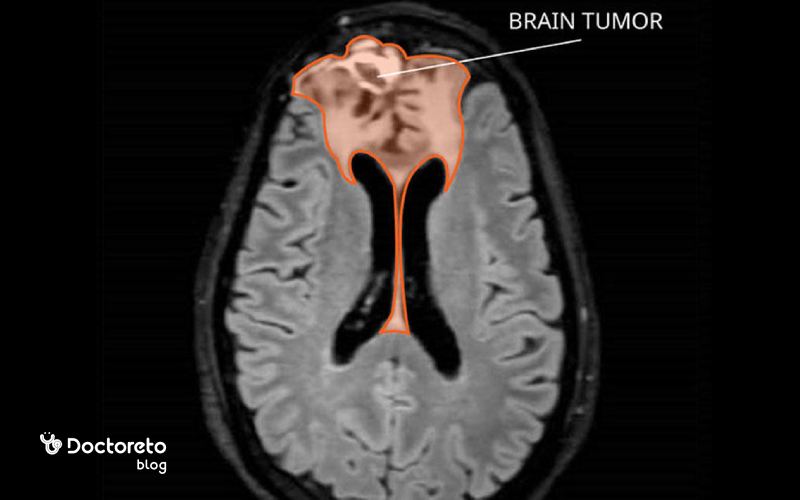

در مراحل پیشرفته، تومور مغزی بدخیم معمولاً در تصاویر MRI یا سی تی اسکن بهصورت تودهای بزرگ، نامنظم و با مرزهای نامشخص دیده میشود. این تومورها اغلب باعث فشار زیاد بر بافتهای اطراف مغز، تورم و جابهجایی ساختارهای طبیعی مغز میشوند. در تصاویر MRI، ممکن است بخشهایی از تومور که دچار نکروز شدهاند، قابل مشاهده باشند و نواحی اطراف آن معمولاً با شدت سیگنال غیرطبیعی نشان داده میشوند.

در این مرحله، بیماران معمولاً علائم شدیدتری مانند سردرد مداوم، تشنج، اختلال در گفتار یا بینایی و تغییرات شخصیتی را تجربه میکنند. تصاویر مراحل پیشرفته معمولاً برای برنامهریزی درمانهای ترکیبی مانند جراحی، رادیوتراپی و شیمیدرمانی استفاده میشوند. تشخیص دقیق از روی عکسها به پزشکان کمک میکند تا میزان گسترش تومور و درگیری نواحی حیاتی مغز را مشخص کرده و بهترین رویکرد درمانی را انتخاب کنند.